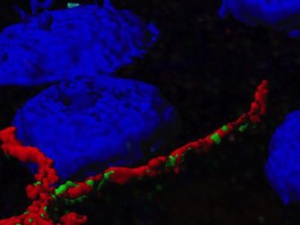

Konfokální mikroskopie umožňuje rychlé a velice kvalitní snímání ve vysokém rozlišení. Získaná data ve formě optických řezů je nutné rekonstruovat a následně analyzovat. Kolokalizační studie (3D colocalization) je spolehlivá metoda, která odhalí strukturní vztahy mezi zobrazovanými objekty.

Konfokální mikroskopie umožňuje rychlé a velice kvalitní snímání ve vysokém rozlišení. Získaná data ve formě optických řezů je nutné rekonstruovat a následně analyzovat. Kolokalizační studie (3D colocalization) je spolehlivá metoda, která odhalí strukturní vztahy mezi zobrazovanými objekty.

V laboratoři Dr. Xaviera Forns (IDIBAPS&NIH) se věnují výzkumu kinetiky viru Hepatitis C pro lepší porozumění průběhu opakované infekce tímto virem po transplantaci jater. Hlavním bodem zájmu bylo porovnání exprese receptoru viru Hepatitis C s celkovou kinetikou infekce.

Tato studie společně s dalšími výsledky ukázala, že množství receptoru viru Hepatitis C v čase transplantace jater reguluje počáteční kinetiku viru. Opakovaná infekce virem Hepatitis C po transplantaci je přímo spojena s množstvím těsných spojů v membránách jaterních buněk.